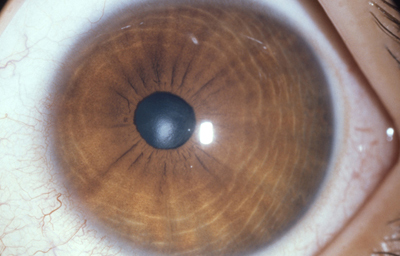

La Atrofia Esencial del Iris. Se produce cuando el endotelio anormal prolifera sobre la superficie del Iris, con subsecuente formación de una membrana contráctil que produce corectopia, atrofia del Iris y policoria falsa; si el endotelio anormal prolifera sobre el ángulo de la cámara anterior genera sinequias y glaucoma.

Atrofia Esencial del Iris - OD de paciente femenina de 36 años

Archivo fotográfico Dr. Carmen Barraquer